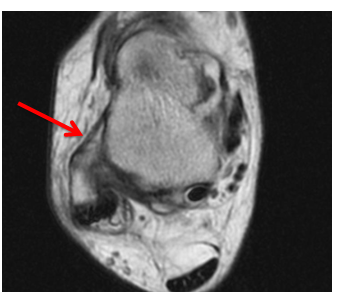

Axial fat saturated proton density MRI image of the right ankle confirmed the presence of fluid effusion around the flexor hallucis longus tendon (Figure 7C). Axial proton density MRI image of the right ankle proved intact muscular tendons and ligaments (Figure 8).

Figure 8 Axial proton density MRI image of the right ankle shows intact anterior talofibular ligament (red arrow).